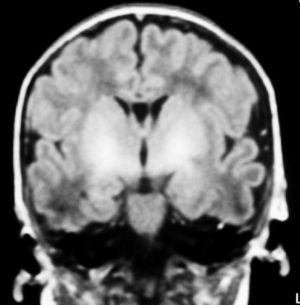

Fig. 4. Resonancia magnética. Secuencia FLAIR en plano coronal. Hiperintensidad de señal bilateral y simétrica localizada en globus pallidus.

A las 48 horas de su ingreso presenta una crisis de hipertonía, motivo por el que se realiza una resonancia magnética.